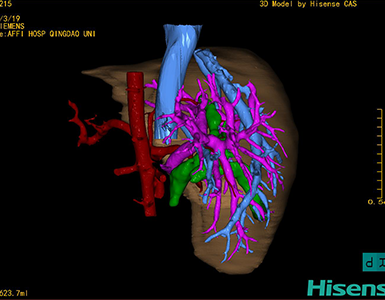

CT结果输入海信CAS系统后行3D重建及手术规划后,于2016-3-22全麻下行“胆总管囊肿切除+胆囊切除+胆总管-空肠吻合术”手术治疗:

术前三维重建及手术方案设计:

将0.625mm双源薄层CT资料的静脉期和动脉期Dicom格式文件导入海信CAS系统。

通过调节窗宽窗位调整CT序号,对肝实质,胆囊,下腔静脉,肿瘤,肝动脉、门静脉及肝静脉等进行三维重建;系统自动计算肝脏体积。

术前手术方案的规划。

术前三维重建:

重建图片